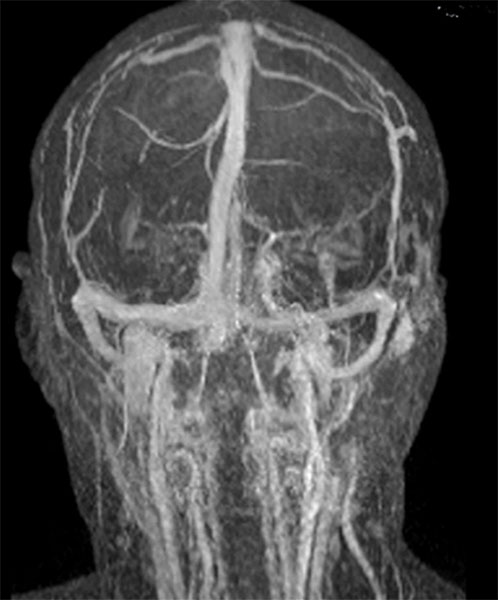

Coronal, contrast-enhanced, dynamic MR angiography, MIP imaging 33 s after injection of the contrast medium. The contrast dynamic is in the venous phase, the venous blood vessels are fully contrasted. The venous malformation itself does not accumulate any contrast medium at this time.

Coronal, contrast-enhanced, dynamic MR angiography, MIP displayed 124 s after injection of the contrast agent, thus a late venous phase. Only now does the venous malformation slowly accumulate some of the contrast medium (“pooling”).